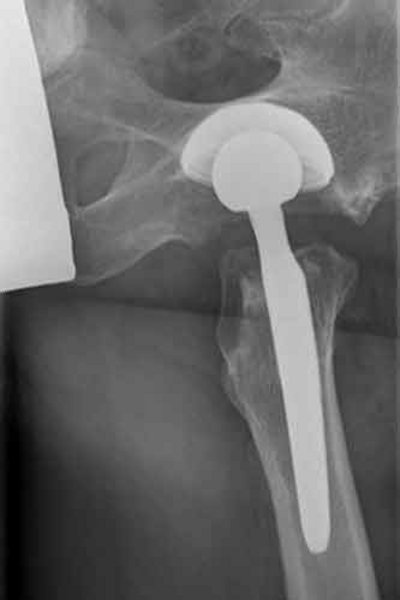

Nachher

Hüftröntgen ap

Fitmore Kurzschaft-Endoprothese mit Allofit Pfanne

Keramik - PE Gleitpaarung